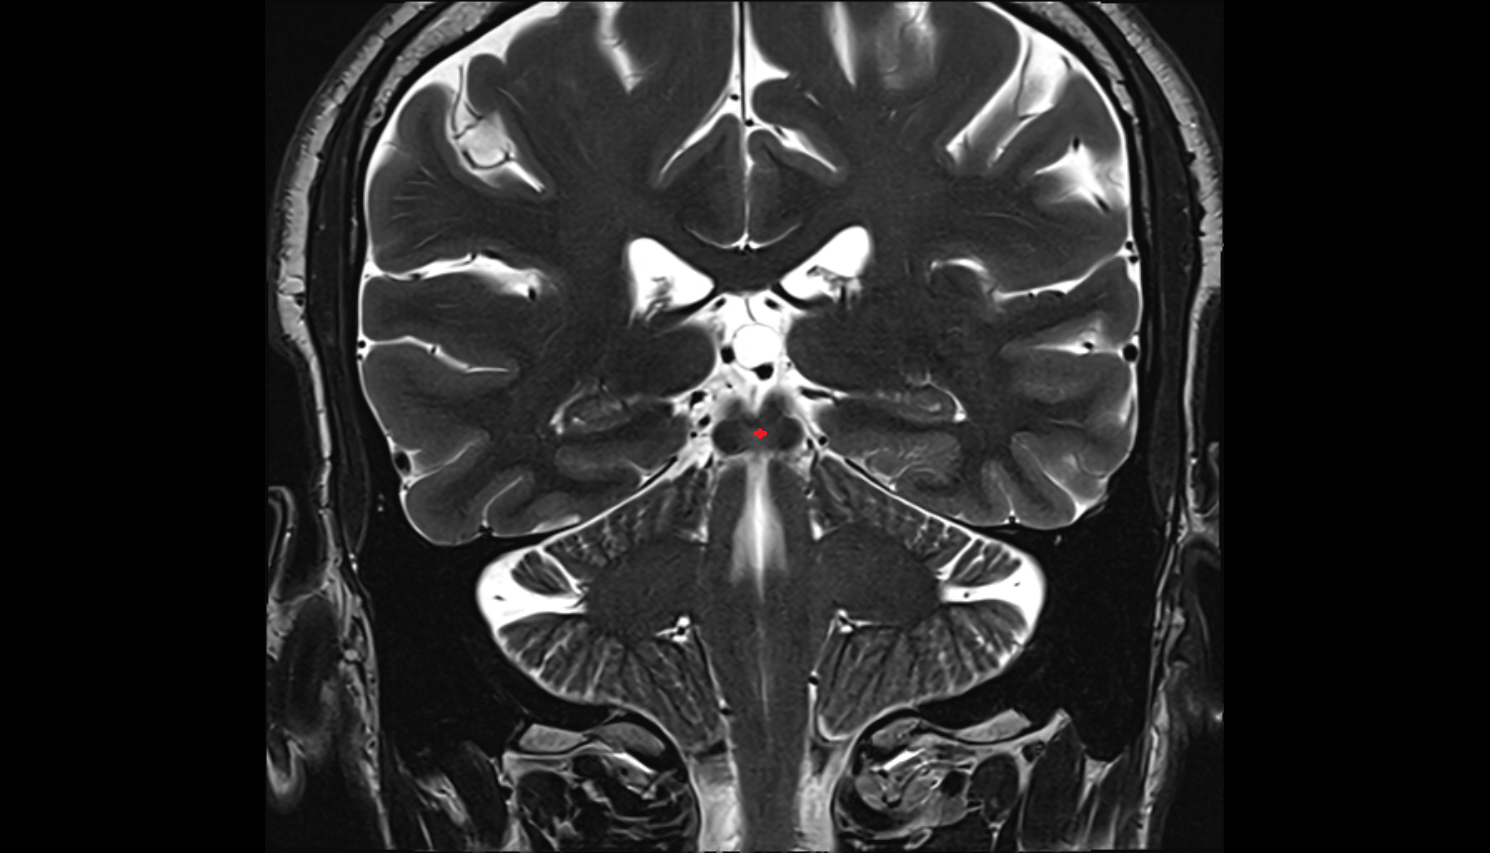

- Hippocampus